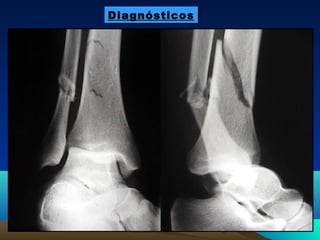

DiagnósticosDiagnósticos